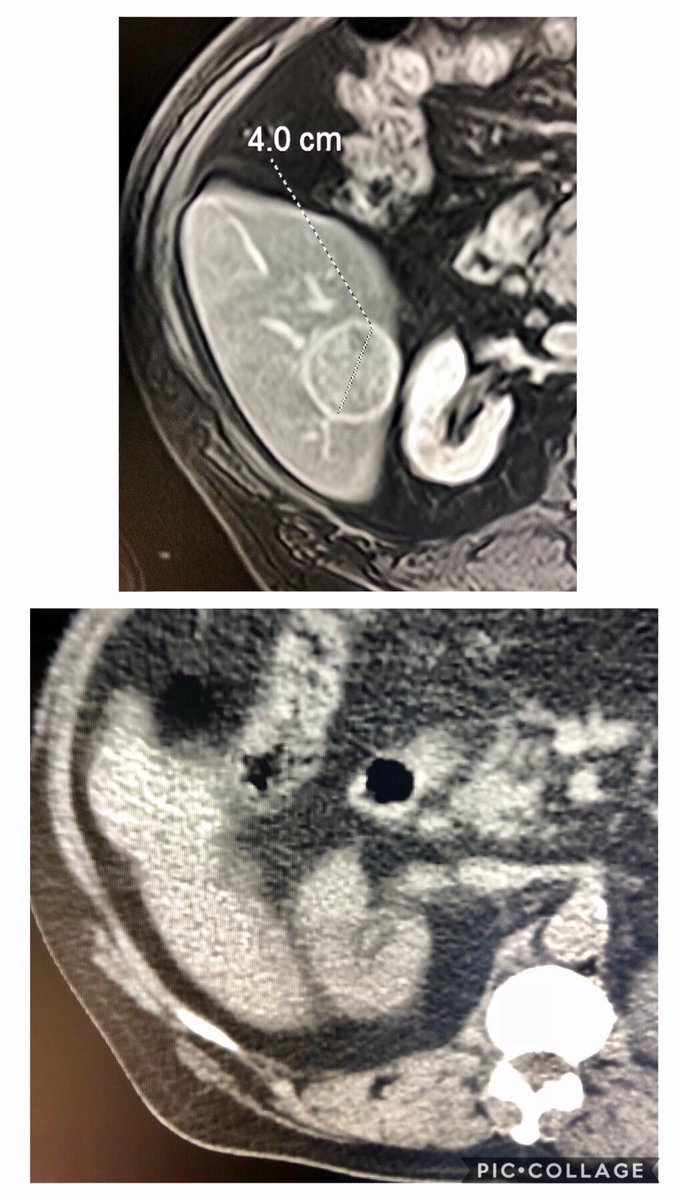

@BTGIO @PresenceHealth 72 M radiation segmentectomy in 2015 Follow up clinic 9/2018 shows no evidence of disease #iRad #y90glass #withoutascalpel #IROnc